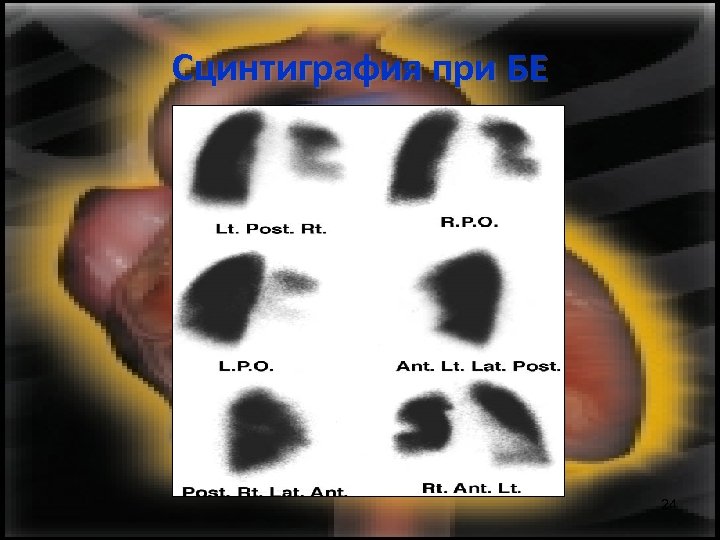

Диагноза • • • Физикално изследване Образно изследване на гръдния кош Белодробна ангиография V/Q – сцинтиграфия Намалено Еt. CO 2 D – димери над 500 mcg/ml Тромбин/АТ III комплекс ЕКГ Ехокардиография 15

Сцинтиграфия при БЕ 24